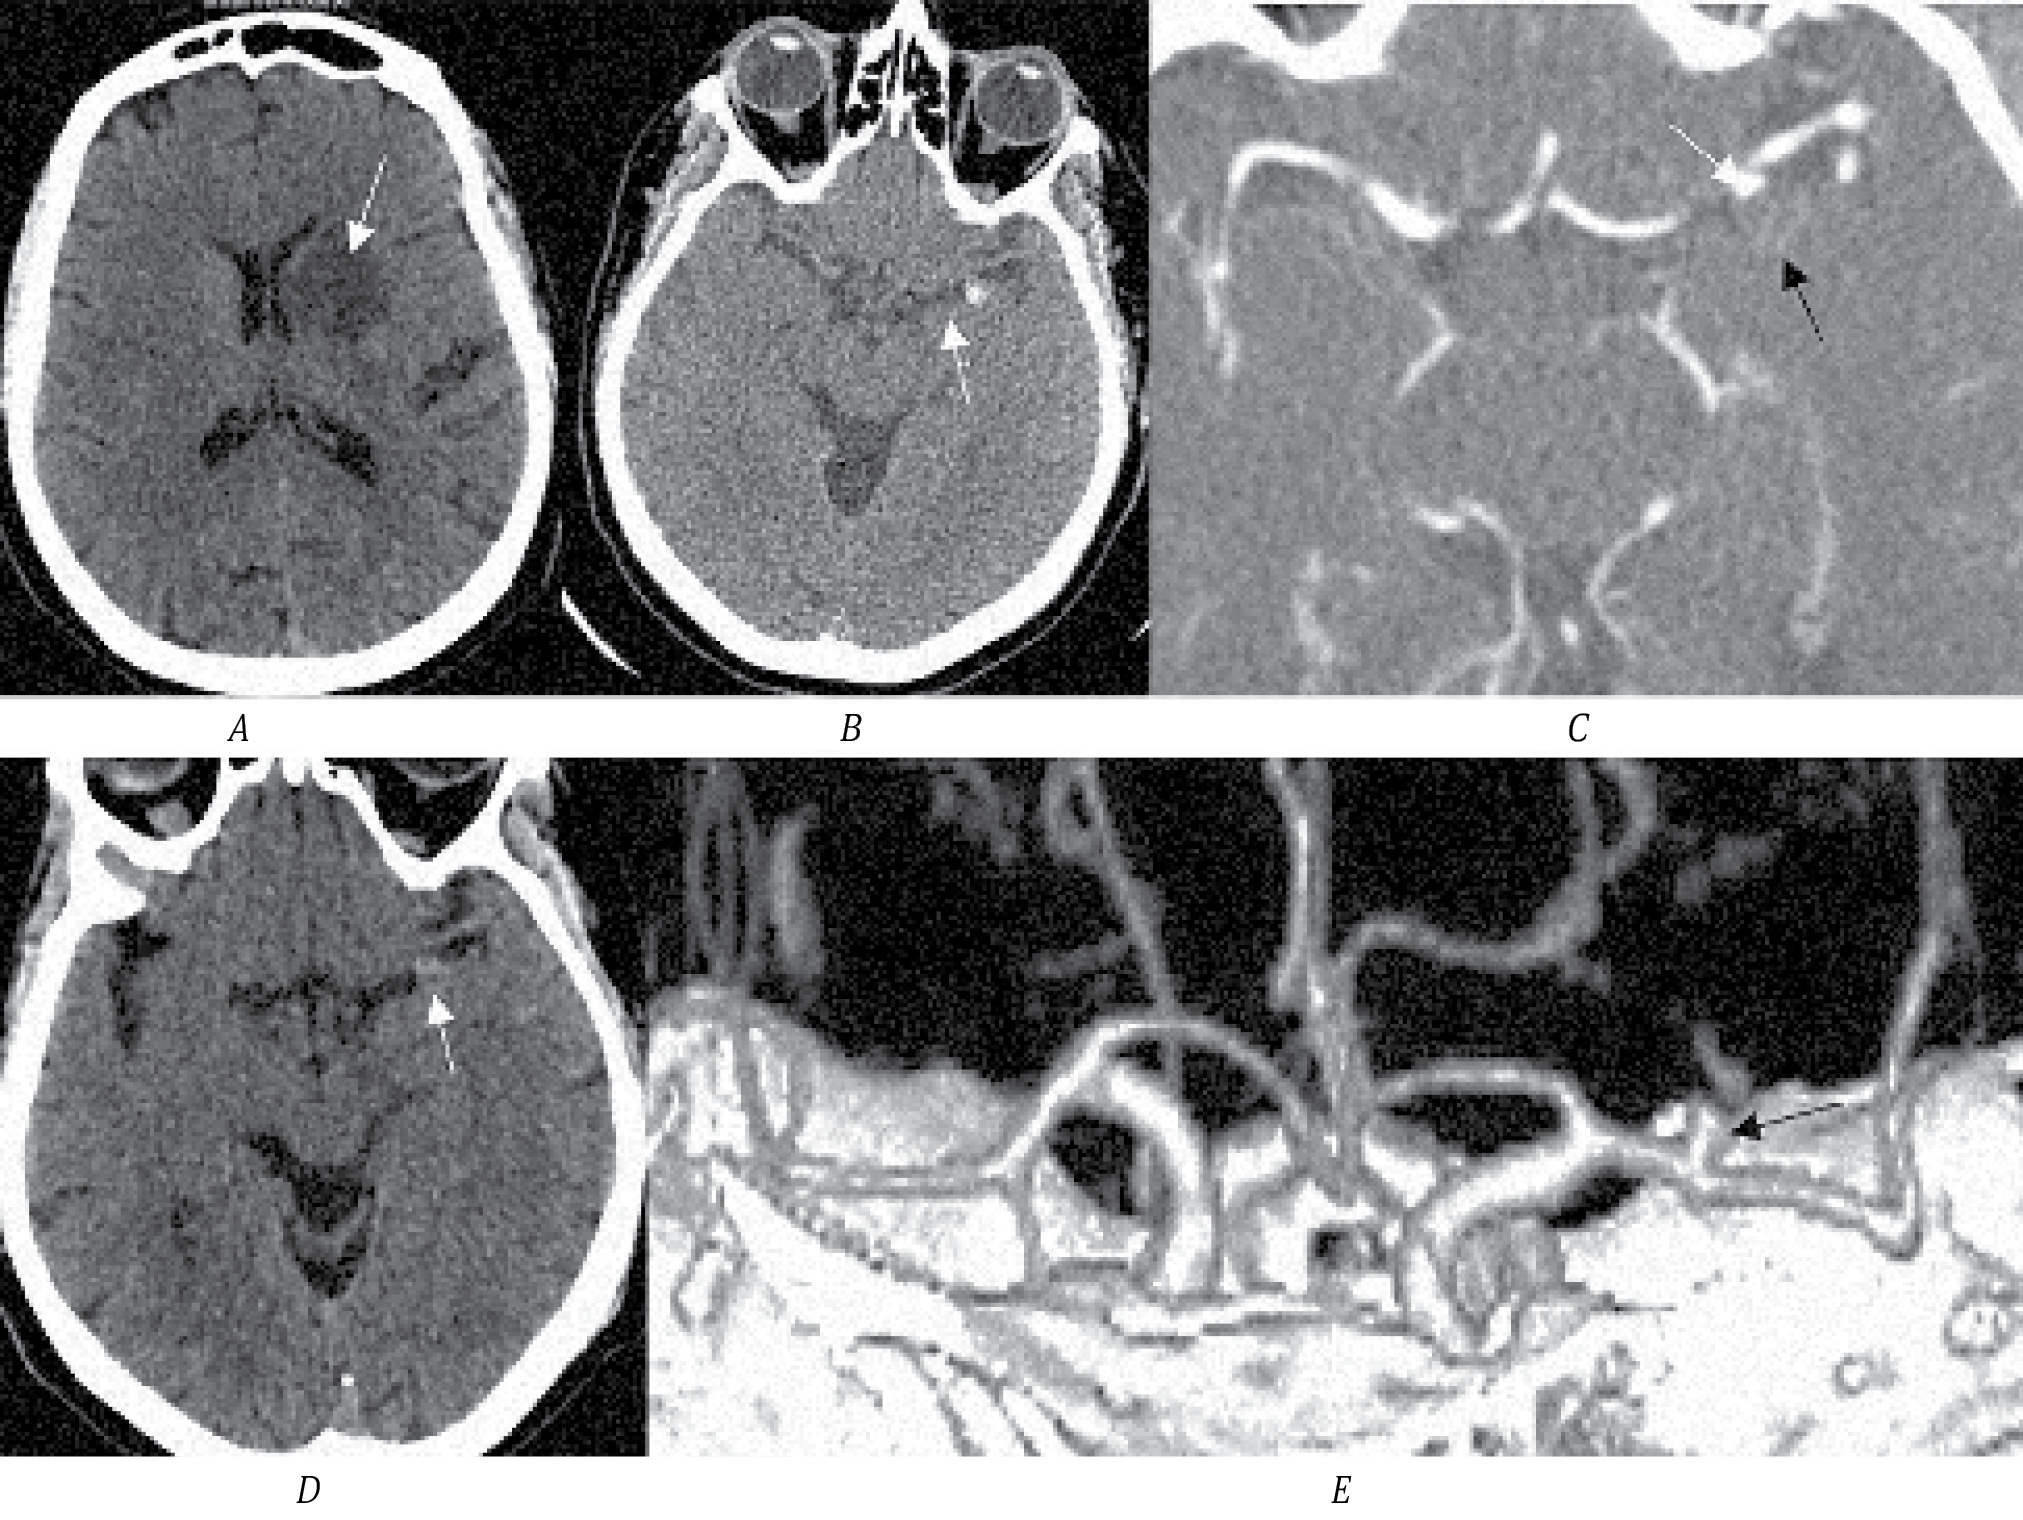

Пациент К., 62 года, поступил в первичное сосудистое отделение с клиникой правостороннего гемипареза (2 балла в руке, 3 — в ноге), моторной афазией, 16 баллов по NIHSS. По МСКТ определяется зона ишемии в левой лобной доле с распространением на подкорковые структуры. По нативному исследованию заподозрена ТА СМА размером до 2 см (рис. 2, А, B). По неясным причинам в первичном сосудистом отделении МСКТ-ангиография не выполнялась. Через 3 мес направлен в региональный сосудистый центр. По МСКТ определяется зона кистозно-атрофических изменений в области перенесённого ИИ в левой лобной доле. По МСКТ-ангиографии определяется небольшая функционирующая часть аневризмы М1-сегмента, дистальные ветви СМА проходимы (рис. 2, C, D).

Рис. 2. МСКТ головного мозга пациента К.

А — МСКТ-натив, определяется зона ишемии в левой лобной доле; B — стрелкой указана ТА СМА с кальцификацией размером до 2 см; C — МСКТ через 3 мес после перенесённого ИИ, определяется зона кистозно-атрофических изменений в левой лобной доле; D — МСКТ-ангиография, белой стрелкой обозначена функционирующая часть аневризмы, чёрной — контур тромбированной части; E — 3D-реконструкция МСКТ-ангиографии, стрелкой указана функционирующая часть аневризмы.

С учётом наличия большого тромбированного мешка аневризмы в области М1-сегмента СМА и развития ишемии в области кровоснабжения лобной М2-ветви СМА вероятна эмболия тромбов из мешка аневризмы. В динамике через 3 мес по ангиографии определяется проходимость всех ветвей СМА, что могло быть связано с наступившей реканализацией тромбированной ветви. При дообследовании других факторов риска ИИ, кроме гипертонической болезни, у пациента не обнаружено. Учитывая высокий риск повторных тромбоэмболических осложнений, выполнили микрохирургическое клипирование аневризмы. После операции состояние пациента декомпенсировалось в связи с развитием энцефалопатии; выписан из стационара с оценкой по модифицированной шкале Рэнкина 4.